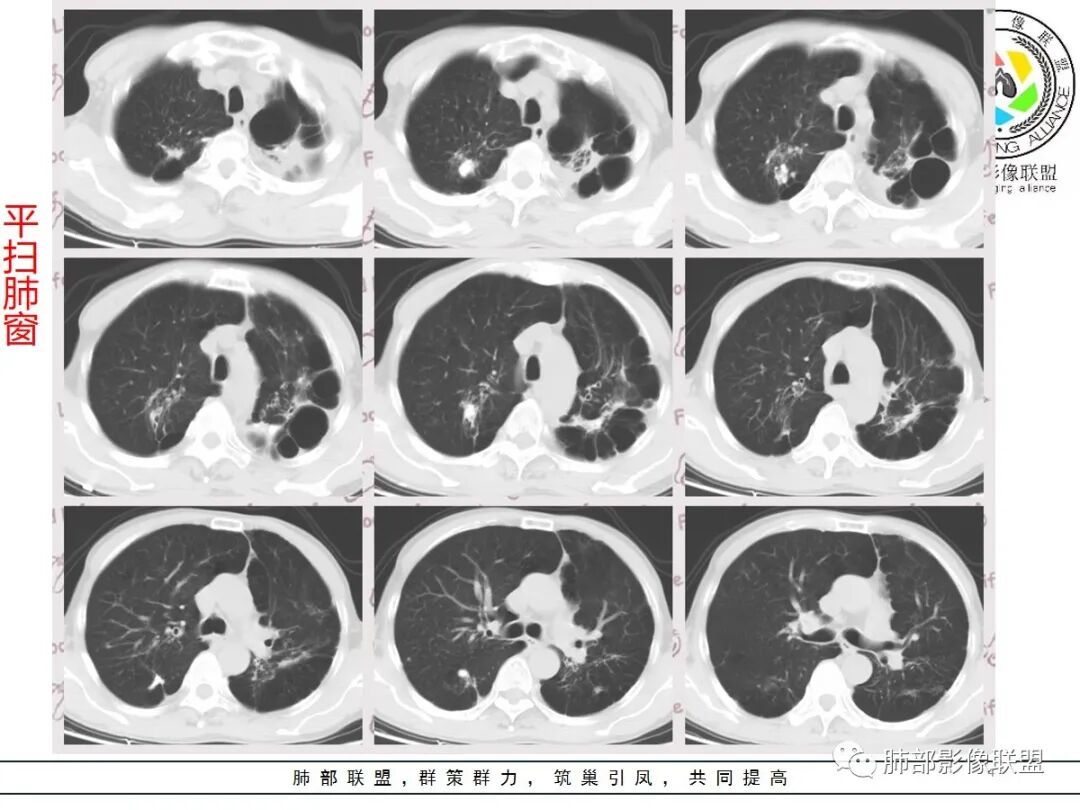

老年男性,肺气肿背景,结核病史。右肺下叶病灶,分叶不明显,局部可疑栽赃,毛刺略呈毛刷感,远端阻塞性肺炎改变,轻微强化,走行血管僵硬,湖泊样坏死,考虑鳞癌。左肺病灶边缘有分叶、毛刺及胸膜牵拉的恶性征象,也有平直收缩的良性征象,可疑卫星灶,这类良恶征象都有判断比较纠结,常规思路:炎性放前边,腺癌待排。

患者老年男性,因咳嗽 咳痰 背痛就诊。既往有喉及肺结核病史。胸部CT:左下肺实性病灶,边缘可见短硬毛刺,分叶,胸膜牵拉,增强可见强化,考虑肺腺癌。

右下肺实性病灶,进入病灶支气管阻塞,支气管壁增厚,病灶内可见坏死,内壁凸凹不平,增强可见病灶强化,考虑恶性病变,鳞癌?

老年男性,结核、慢性病史,肺气肿背景,右肺胸膜下肿块影,边界清晰,边缘膨隆,中度环形强化,内见边界清晰坏死区,并见部分强化小血管,鳞癌破坏力强,而且病灶一侧支气管受推移,首先考虑右肺结核,鉴别鳞癌,左肺考虑腺癌,胸膜牵拉,膨隆生长,边缘毛刺样,潜在分叶。

老年男性,既往肺结核病史。肺气肿背景,可见钙化灶及条索影。右肺下叶胸膜类圆形占位,边界清晰,内部可见边界清晰的坏死区,轻度强化,考虑为结核可能;左肺下叶结节,可见分叶,毛刺,胸膜牵拉,增强可见强化,考虑为恶性,腺癌可能。

左肺肺气肿,双肺多发结节,上肺多发纤维索条影及钙化,符合陈旧性结核病变。右肺下叶结块,边缘毛糙,内部可见低密度坏死,环形强化,坏死边界清楚,考虑脓肿,OP。左肺下叶结节,边缘可见毛刺,深分叶,边缘收缩,远端牵拉胸膜,考虑肺癌,腺癌。

老年男性,肺气肿背景,左肺下叶结节,深分叶,毛刺,胸膜牵拉,内部可见坏死,坏死边界不清,不均匀强化。右肺下叶大肿块,边缘有毛刺,多发小灶性坏死,胸膜下有侵犯,考虑恶性,左肺下叶腺癌,右肺下叶低分化鳞癌。

男,64岁,咳嗽咳痰,气喘10余年,右肺下叶软组织密度肿块影,边界清晰,边缘见细短毛刺及分叶,轻度胸膜粘连,病灶内密度不均,增强扫描看见坏死区,病灶边缘明显强化,考虑鳞癌可能。左肺下叶病灶深分叶、毛刺、胸膜牵拉,考虑腺癌可能,除外转移性病变。

双肺陈旧性肺结核,肺气肿背景。右肺下叶肿块,边缘毛糙,内部可见大片低密度坏死,环形强化,坏死边界清楚,考虑鳞癌。左肺下叶结节,边缘可见毛刺,深分叶,有收缩,有膨隆,胸膜牵拉,考虑腺癌。